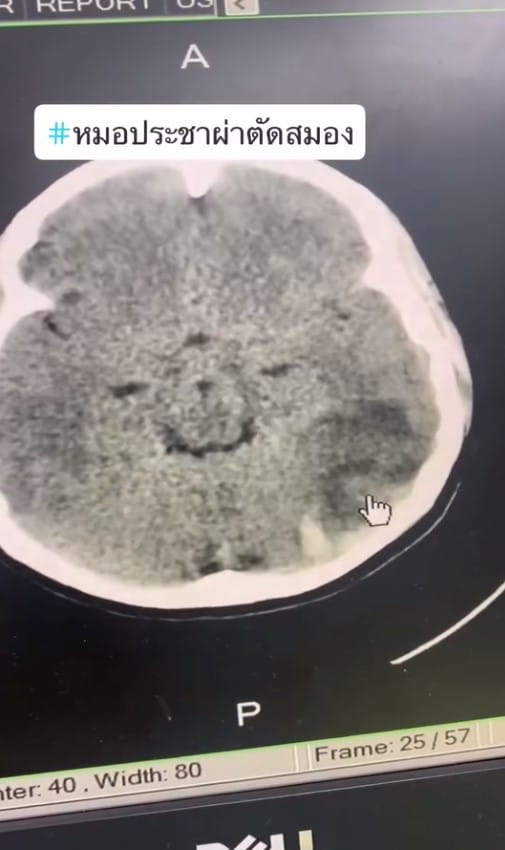

“ใครที่กินยาคุมอยู่ฟังให้จบนะครับ ผู้ป่วยหญิงอายุ 32 ปี ปวดศีรษะรุนแรง 3 วัน” นพ.ประชา กล่าวพร้อมเปิดตัวอย่างภาพเอ็กซ์เรย์ของผู้ป่วยให้ดูถึงความผิดปกติ พร้อมระบุว่า..

“ปวดหัว 3 วัน วันที่สองมาฉีดยาแก้ปวด กลับไปปวดมากกว่าเดิมและตามองไม่ชัด ลักษณะการบวมและเส้นเลือดแตกแบบนี้ เป็นจากเส้นเลือดใหญ่ที่ตันไปครับ เส้นเลือดใหญ่ก็เหมือนท่อประปาที่วิ่งเข้าบ้าน เส้นเลือดดำเหมือนท่อน้ำทิ้ง”

แต่จากภาพเอ็กซ์เรย์ของผู้ป่วยรายนี้พบว่า เส้นเลือดดำข้างซ้ายได้หายไปจากฟิมล์เอ็กซ์เรย์ นั่นก็เพราะมันตันไปแล้ว ทำให้สมองบวมเป่ง พอแรงดันสูงขึ้นสมองก็เริ่มปริและระเบิดเป็นก้อนเลือด